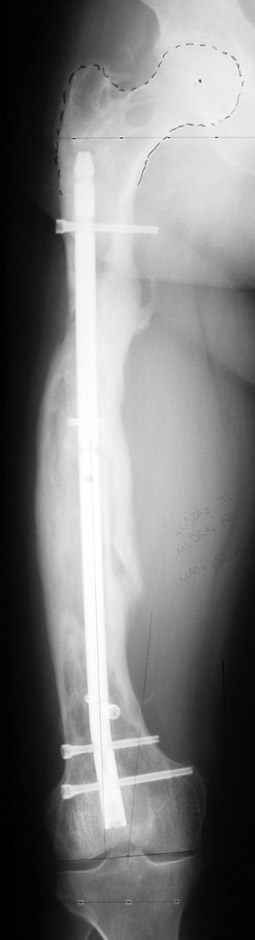

Eksternal fiksatör ile geçen süre (eksternal fiksasyon indeksi), gereken distraksiyon miktarına bağlıdır ve bu süre boyunca bazı komplikasyonlarla karşılaşılabilir. Distraksiyon dönemi sona erdikten sonra, distraksiyon süresinin iki katını aşan konsolidasyon döneminde hastalar eksternal fiksatörü zorlukla tolere edebilirler. Yeterli konsolidasyon sağlanmadan eksternal fiksatör çıkartılırsa ise kırıklar, deformite ve kısalık oluşabilir. Hastanın fiksatör ile birlikte geçirdiği sürenin azaltılması ve böylece hasta konforunun ve aktivite düzeyinin arttırılması için intramedüller çivi üzerinden uzatma yöntemi uygulanmaktadır. Bu yöntemde distraksiyon dönemi sona erdiğinde kemiğin içindeki çivi statik olarak kilitlenmekte ve eksternal fiksatör çıkartılmaktadır. Stabilizasyon intramedüller çivi tarafından sağlandıktan sonra konsolidasyon dönemi gerçekleşmektedir. Bu şekilde hem eksternal fiksatörün uzun süre kalmasından hem de erken çıkartılmasından kaynaklanan komplikasyonların önüne geçilmektedir.

Vaka 2